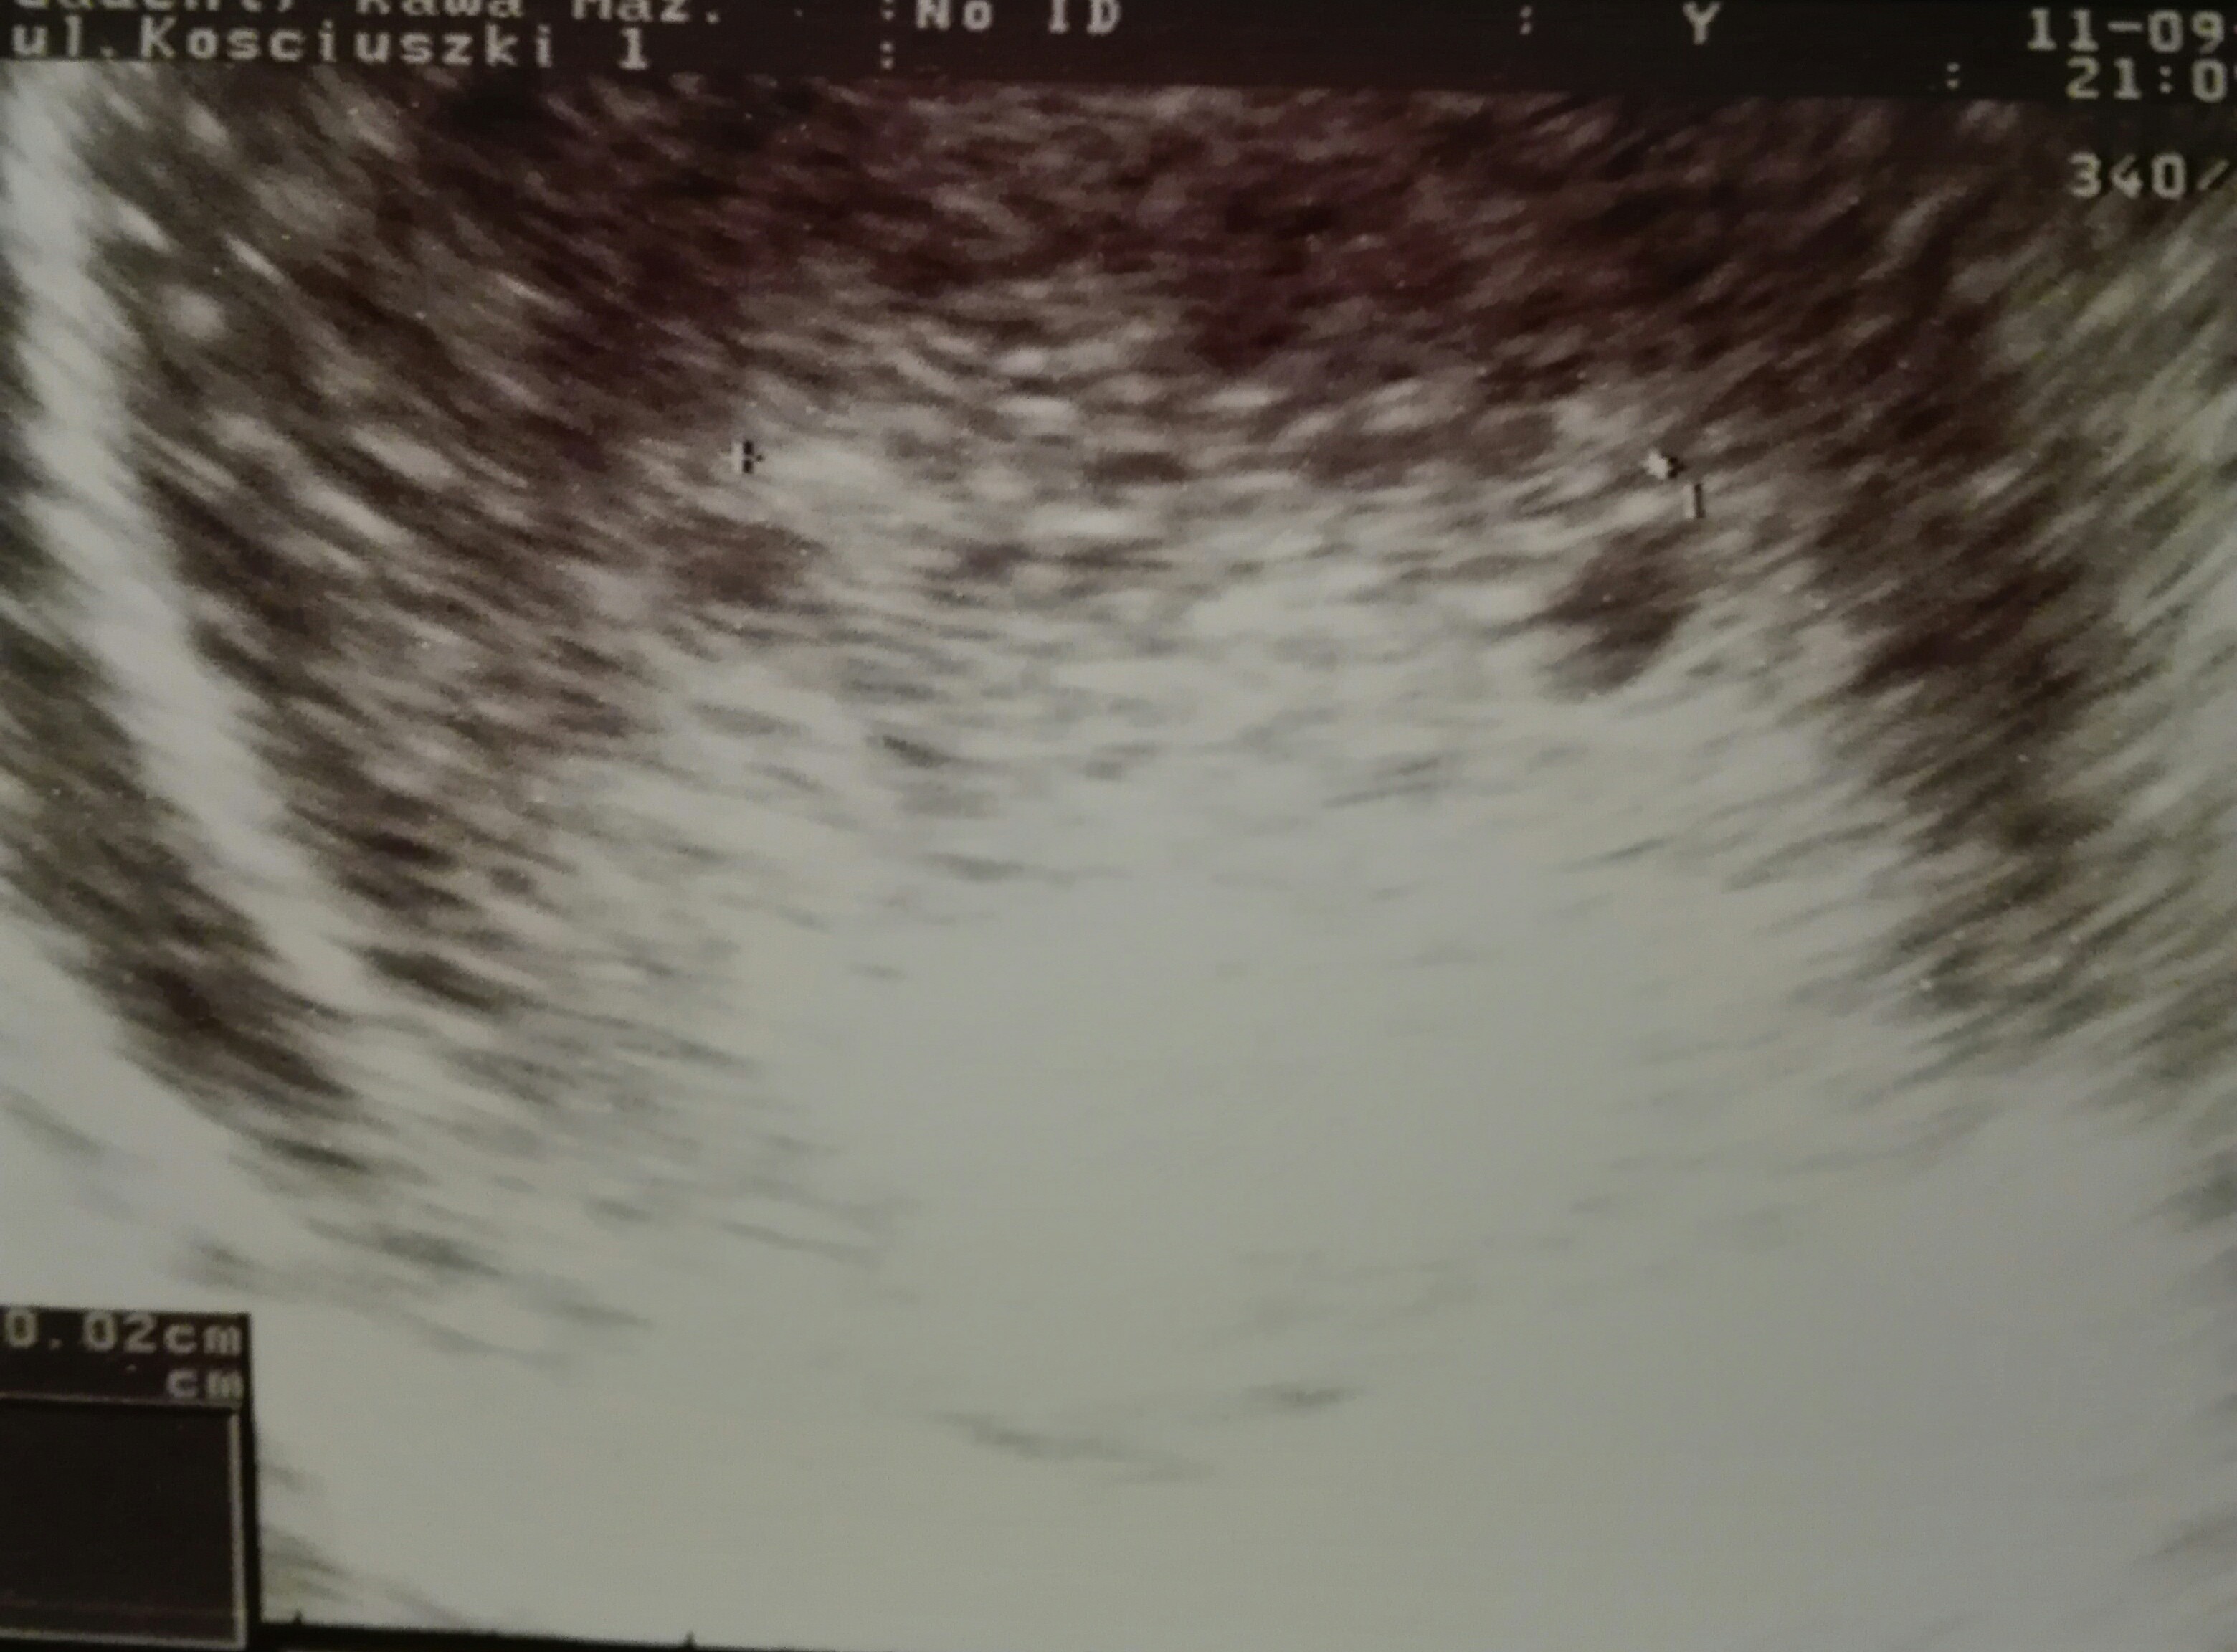

Nie wiem jeszcze, za szybko na plec, pewnie na nastepnej wizycie tez jeszcze nie bedzie widac. Teraz maluszek nawet sie jeszcze nie ruszal :( ale serduszko bije, to najwazniejsze i maluszek rosnie.

Justyna super, pierwsza fotka, i gratuluję serduszka maluszka[emoji173][emoji173]

IMG_20180911_205701.jpg